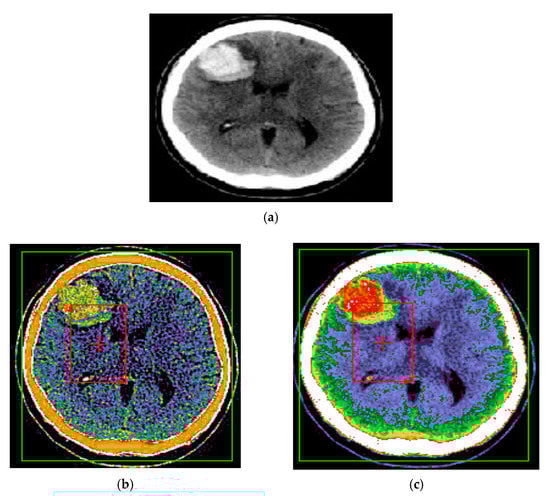

The method of improving the contours and textures of images resulting from processing with the Wiener filter proposed in the article (Figure 4), followed by the application of the NCN algorithm, using the AB template, improves the contours of images by equalizing and adapting the histogram. Additionally, the evaluation of the performance of the processing process presented above can be done if we evaluate the image resulting after edge detection, for an initial image without noise but with low contrast, the image obtained by global scaling and the image obtained after preprocessing with AB template (Figure 5 and Figure 6). Thus, it is found that edge detection is correct and robust only in the image obtained by global scaling and in the image obtained after preprocessing with the AB template.

The proposed method for improving images with modified Wiener filter and nonlinear cellular network can be applied with success also with low contrast CT (computer tomograph) images. The improvement of tomographic image quality aims at obtaining superior visibility of the image components, the adaptive increase of the contrast, in order to be interpreted as easily as possible by the specialist doctor. Figure 7, Figure 8 and Figure 9 show the results obtained in the case of such images.

The interest in such filters is determined by the fact that much of the existing information in the images is provided by contours, and most of the noise removal methods cause them to fade. In the present case, at the cost of removing a smaller amount of noise in the contour-containing regions, it can be better preserved, as shown by the results shown in Figure 7, Figure 8 and Figure 9. There is thus a trade-off between the amount of noise removed and the quality of preserving the contours in the image.

It should be noted that in the results presented in Figure 8 and Figure 9, the noise reduction is accompanied by an improvement of the contours of the processed image, leading to a microscopic analysis, highlighting very well the contours of tumor formations from diseased tissues to healthy tissues. Such an estimate is useful for the medical act, especially for surgery. Additionally, the proposed method, in addition to the contour enhancement property, highlights the deconvolution applications for removing or reducing the blurring of energy areas in images by highlighting their vascularization elements (Figure 8 and Figure 9).

Figure 8. (a) Initial image with low contrast; (b) improved image—CT cranial layer image processed with modified Wiener filter; (c) CT cranial layer image processed with the combined algorithm between the modified Wiener filter and the nonlinear cellular network.